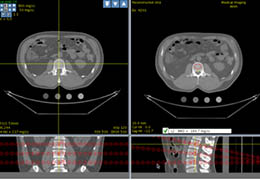

View X-Ray CT & MRI Scans Fast and Easily

Traditional multi-planar slicing

Multi-planar slicing.

Oblique slicing.

Side-by-side comparative assessment for pre- and post-operative scans.